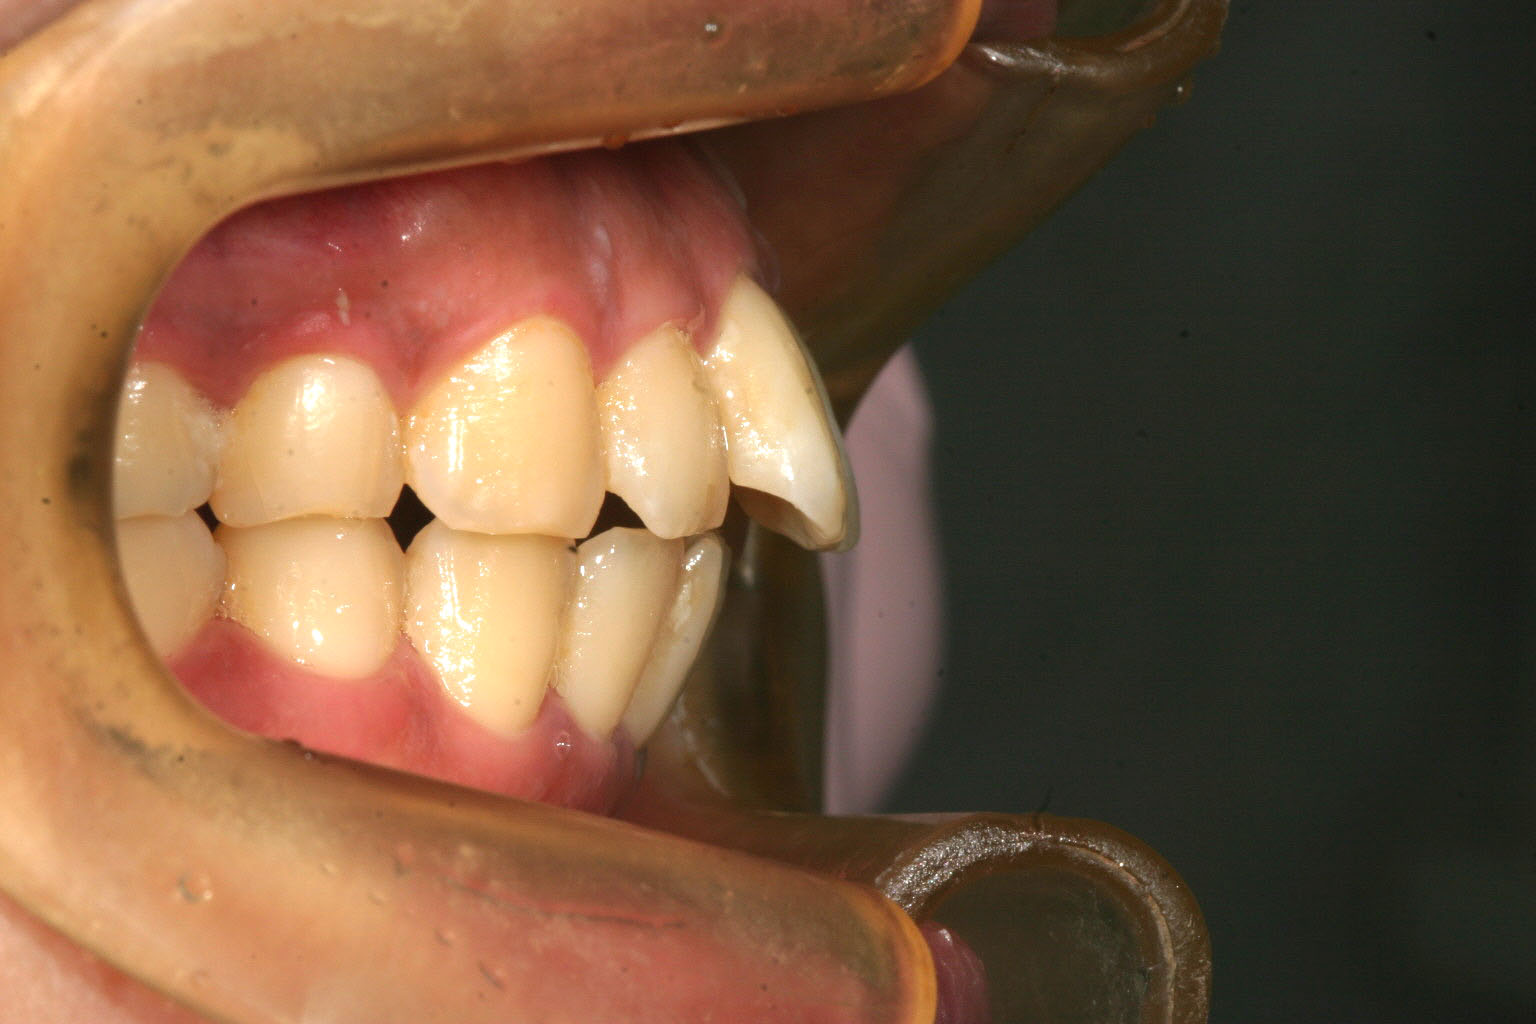

アーチが狭いお陰で前歯が前突しています。

側面観は少し出っ歯が目立ちます。